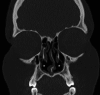

Figure 2. Coronal view CT scan of the sinus showing the bilateral agenesis of the head of the inferior turbinates

The asterisk represents the agenesis of the head inferior turbinate. CT: computed tomography